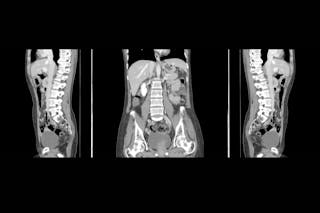

tomografia computadorizada (CT)

esta técnica utiliza um feixe de raios x para produzir imagens transversais do corpo humano. Quando o processo de imagem está ocorrendo, o tubo de raios-x emite continuamente um feixe de raios-x e está girando em um círculo de 360 graus em um dispositivo chamado pórtice.

Enquanto isso está acontecendo, o paciente está deitado em uma tabela de imagem CT especial que está permitindo o raio-x através. O raio-x é em forma semelhante a um ventilador portátil e é muitas vezes descrito como um feixe de ventoinha. Há múltiplos Detectores digitais localizados dentro deste guindaste circular que continuamente identificam a energia dos fótons de raios-x que saem do paciente.

o movimento da mesa e do paciente que se move através do pórtico permite a reconstrução de imagens como fatias (ou tomógrafos) de tecido humano. O exame de tomografia computadorizada mais comum é examinar o peito, abdômen e pélvis de um paciente, e a razão mais comum para isso é identificar a propagação do câncer. “Corantes de raio-X “são injetados em pacientes para identificar o câncer quando usando tomografia computadorizada, como o tecido do câncer vai absorver o” corante de raio-x ” e ser mais óbvio na imagem.

com técnicas de imagiologia de rotina CT, não deve haver quaisquer riscos ou perigos para os doentes a partir dos níveis de radiação utilizados.